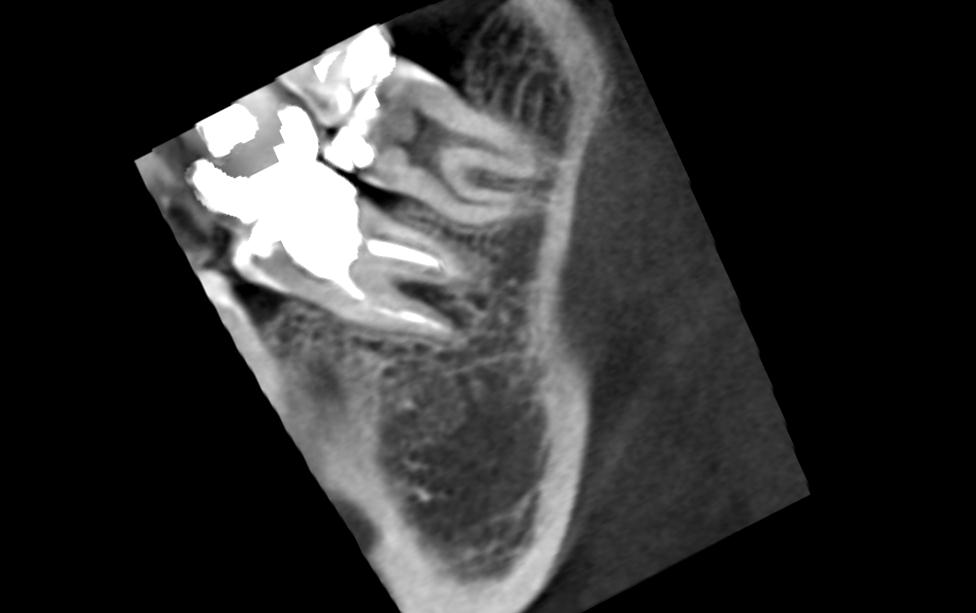

А вот такие снимки чтото скажут:Нажмите на изображение для увеличения

ID:	4314303Нажмите на изображение для увеличения

Название: Image4.jpg

Просмотров: 72

Размер:	32.0 Кб

ID:	4314304Нажмите на изображение для увеличения

Ну в чем же вода - все сходятся на том, что надо удалять. Не затягивая, т.к свищ по проекции межкорневой гранулемы и грануляции сособсвуют разрушению кости, чем дальше, тем больше... И потом тяжело будет имплант ставить... Куда уж конкретнее?!?